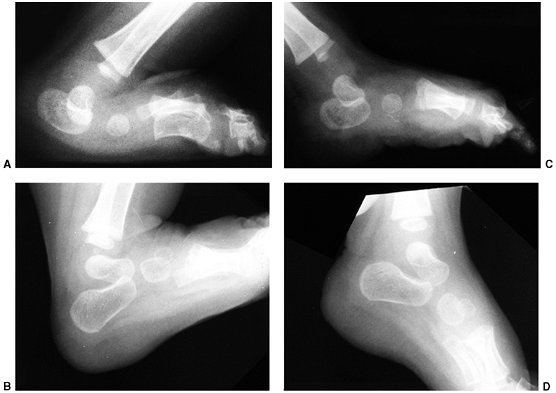

The anterioposterior view is obtained with the foot pressed against a

maximally and held in a position of external rotation (37,45) (Fig. 30.8).

The talus to first metatarsal angle is measured on both the

anteroposterior and lateral views, with increasing angles indicating

more severe deformity. As the navicular is not ossified, there is no

direct measurement of the position of this bone relative to the long

axis of the talus (46). The axis of the talus

and the calcaneus usually converge, and the axis of the talus and the

first metatarsal form a straight line in the healthy state. The degree

of divergence from this linear alignment represents the intrinsic

deformity of the clubfoot (46). With

dorsiflexion, the long axis of the talus and the calcaneus remain

parallel, and the calcaneus remains plantar-flexed relative to the long

axis of the talus (Fig. 30.8). The alignment of the calcaneus and the cuboid is assessed on the anterioposterior view.

![]() |

|

Figure 30.8 A: Simulated weight-bearing anteroposterior radiograph of clubfoot. The talus (small straight arrow) and calcaneus (large straight arrow)

are parallel, rather than divergent. The metatarsals are markedly adducted in relation to the talus. The cuboid ossification center (curved arrow) is medially aligned on the end of the calcaneus, rather than in the normal straight alignment. B: Maximum dorsiflexion lateral radiograph of clubfoot. The talus and calcaneus are somewhat parallel to each other and plantar-flexed in relation to the tibia. |